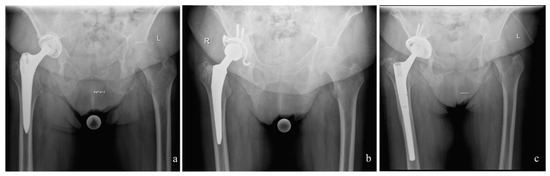

2. Material and Methods

2.3. Surgical Procedure